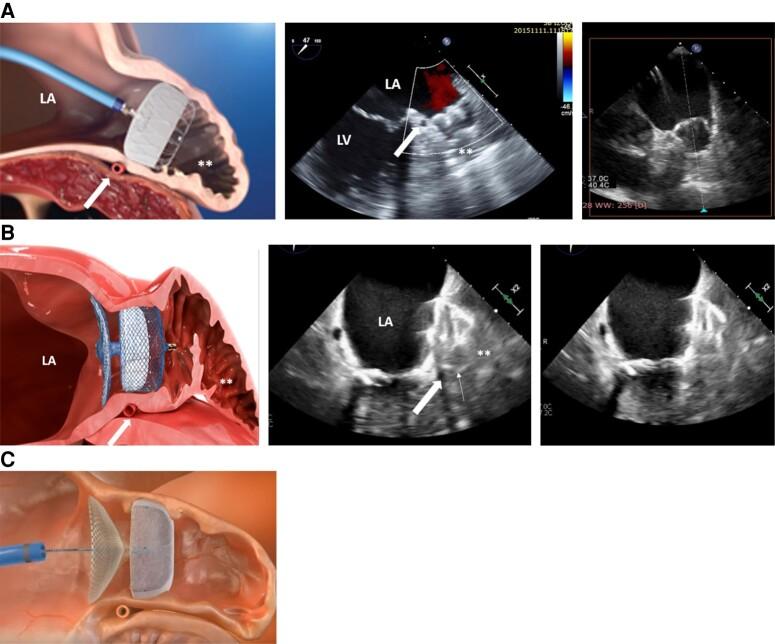

实用的左心耳封堵术非植入医师指南:国际共识文件。

Practical guide on left atrial appendage closure for the non-implanting physician: an international consensus paper.

A significant proportion of patients who suffer from atrial fibrillation (AF) and are in need of thromboembolic protection are not treated with oral anticoagulation or discontinue this treatment shortly after its initiation. This undertreatment has not improved sufficiently despite the availability of direct oral anticoagulants which are associated with less major bleeding than vitamin K antagonists. Multiple reasons account for this, including bleeding events or ischaemic strokes whilst on anticoagulation, a serious risk of bleeding events, poor treatment compliance despite best educational attempts, or aversion to drug therapy. An alternative interventional therapy, which is not associated with long-term bleeding and is as effective as vitamin K anticoagulation, was introduced over 20 years ago. Because of significant improvements in procedural safety over the years, left atrial appendage closure, predominantly achieved using a catheter-based, device implantation approach, is increasingly favoured for the prevention of thromboembolic events in patients who cannot achieve effective anticoagulation. This management strategy is well known to the interventional cardiologist/electrophysiologist but is not more widely appreciated within cardiology or internal medicine. This article introduces the devices and briefly explains the implantation technique. The indications and device follow-up are more comprehensively described. Almost all physicians who care for adult patients will have many with AF. This practical guide, written within guideline/guidance boundaries, is aimed at those non-implanting physicians who may need to refer patients for consideration of this new therapy, which is becoming increasingly popular.

相当一部分患有心房颤动 (AF) 且需要血栓栓塞保护的患者未接受口服抗凝治疗或在开始治疗后不久就停止了治疗。尽管有直接口服抗凝剂可用,其大出血风险低于维生素 K 拮抗剂,但这种治疗不足的情况并未得到充分改善。导致这种情况的原因有很多,包括抗凝期间发生出血事件或缺血性中风、严重出血事件风险、尽管进行了最佳的教育尝试但治疗依从性仍差、或对药物治疗的反感。一种替代的介入治疗方法,它与长期出血无关,与维生素 K 抗凝一样有效,20 多年前就已经引入。由于多年来程序安全性的显著提高,主要通过导管植入设备的方法进行的左心耳封堵术,越来越多地用于预防不能有效抗凝的患者发生血栓栓塞事件。这种管理策略为介入心脏病学家/电生理学家所熟知,但在心脏病学或内科中并未得到更广泛的认可。本文介绍了相关设备并简要解释了植入技术。适应证和设备随访得到了更全面的描述。几乎所有照顾成年患者的医生都会有很多患有 AF 的患者。本实用指南在指南/指导方针的范围内编写,旨在为那些可能需要转介患者考虑这种新疗法的非植入医生提供帮助,这种疗法越来越受欢迎。